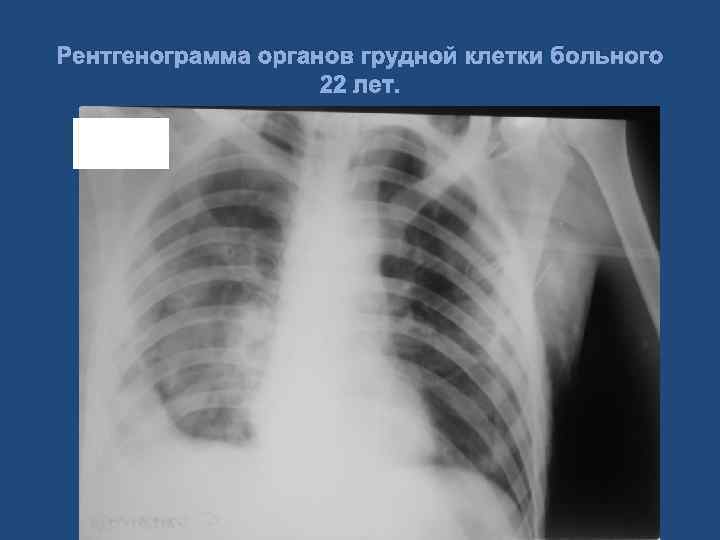

Клиническое наблюдение. Больной 22 лет. Диагноз: Тяжелая сочетанная травма. Тупая травма грудной клетки, двусторонний посттравматический гемопневмоторакс. Тупая травма живота, множественные разрывы правой доли печени, гемоперитонеум. Геморрагический шок Ш ст. 63

Рентгенограмма органов грудной клетки больного 22 лет.